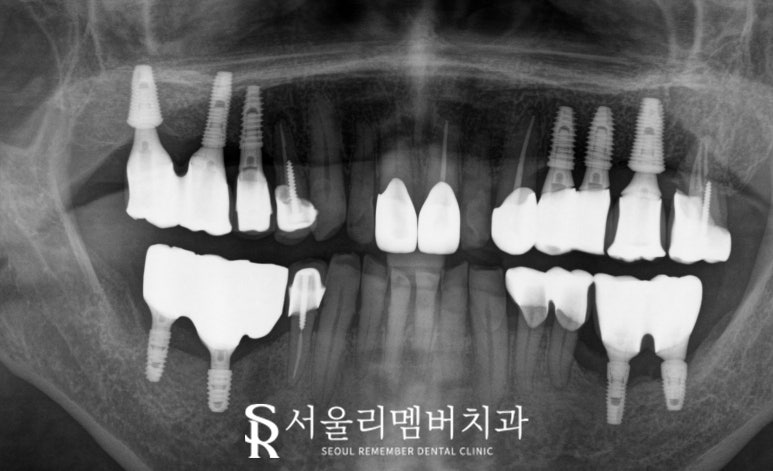

치료가 끝난 후 엑스레이로 최종 결과를 분석한 후,

임플란트가 안정적으로 자리 잡았으며

기존 브릿지로 인한 통증도 해결되어

구강 환경이 크게 개선된 것을 확인했습니다.

치경부 마모로 처치한 앞니 부위도

건강하고 자연스러운 미소를 되찾게 되었죠.

치경부 마모로 인해 처치가 필요했던

앞니 부위는 크라운으로 수복하여

더욱 건강하고 미소가 아름다워진 모습이네요.